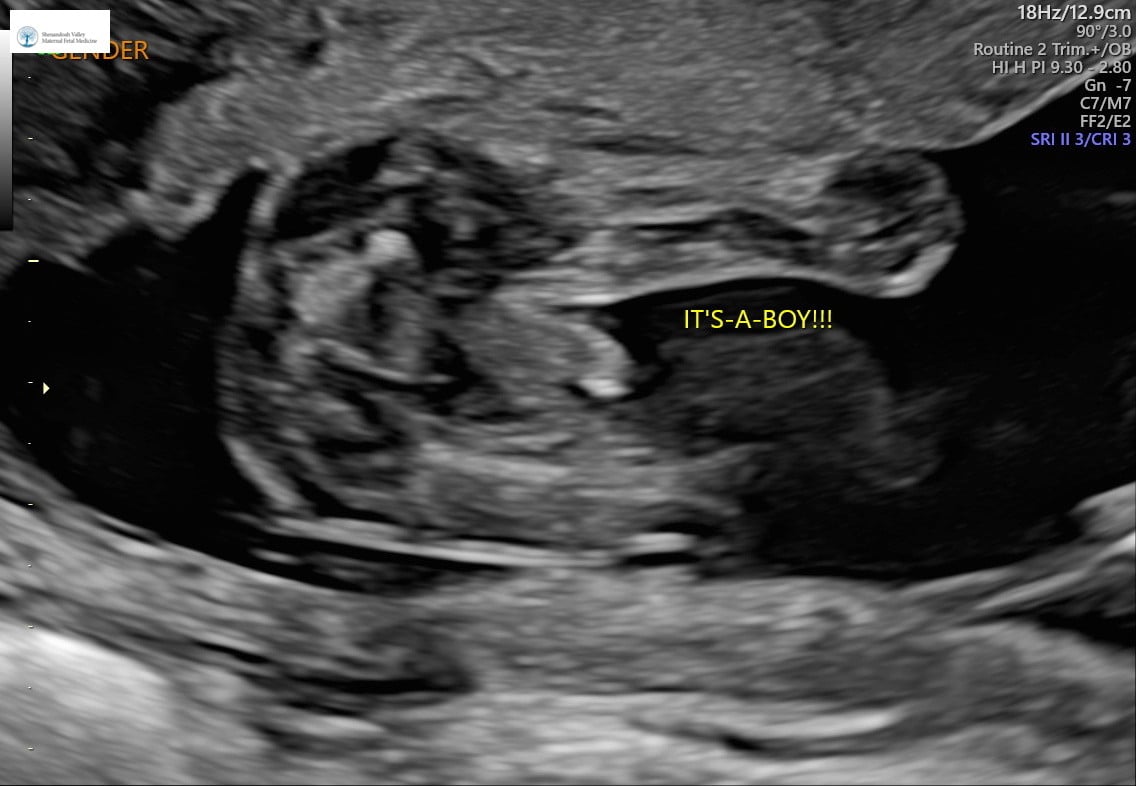

Had a private ultrasound today at 15+1 and we’re having baby boy #3!!! I’m so excited, we have everything and I love being a boy mom! He even waved at us during our ultrasound!